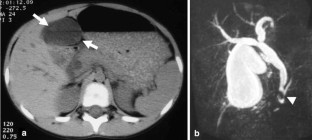

Fig. 1